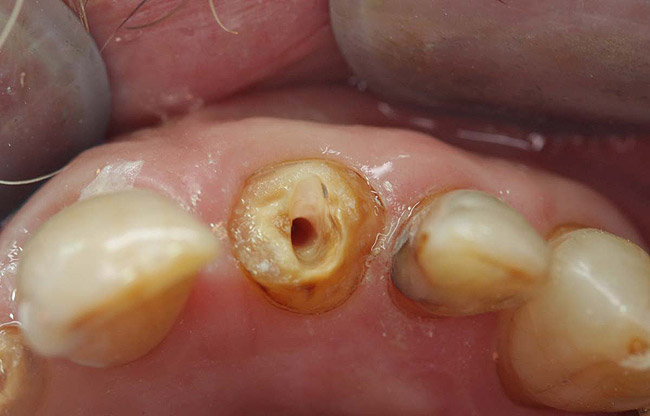

Case 1

A Class IN maxillary bicuspid was previously restored with a fiber post and an all-porcelain crown (Figure 1). The forces of the oral environment resulted in fracture of the fiber post and crown failure. The remaining fiber post in the root was removed, and anti-rotational areas were prepared for a cast post (Figure 2). A gold cast post was constructed at a dental laboratory, using an indirect technique (Figure 3). A porcelain-fused-to-metal (PFM) crown was constructed with a bevel finish to provide a ferrule and reduce forces on the post (Figure 4 and Figure 5).

Figure 6  Endodontically treated maxillary right second molar.

Figure 6

Figure 7  Second molar with the palatal canal prepared for post placement.

Figure 7